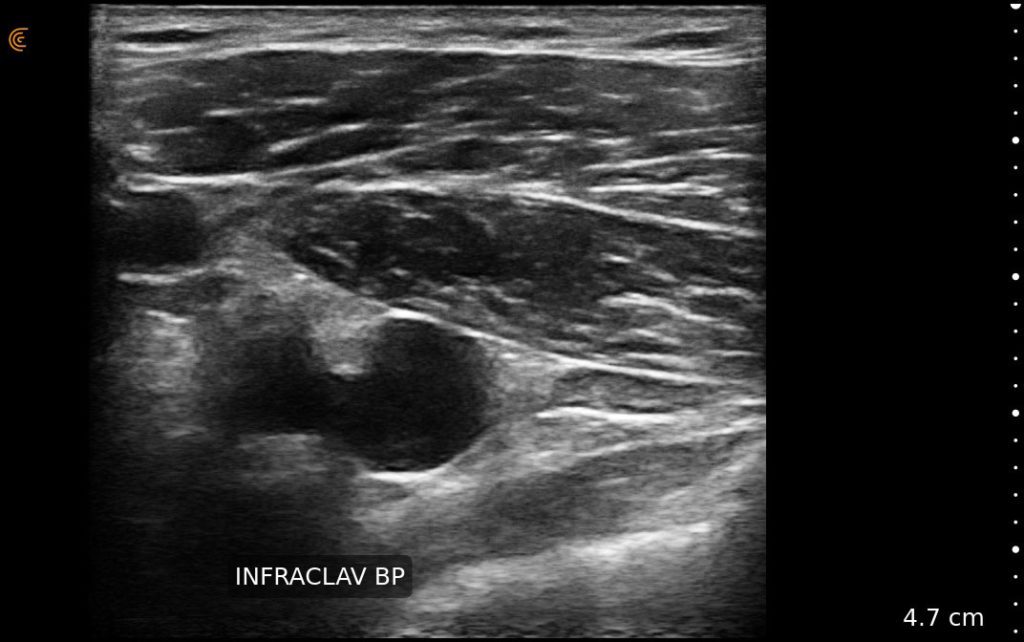

With high-definition imaging comparable to traditional systems, Clarius is the ultimate wireless ultrasound scanner for safe regional nerve blocks and post-operative follow-up.

Now with our wireless Clarius Ultrasound Scanner, we can connect to our iPads and iPhones very easily and take it with us anywhere.